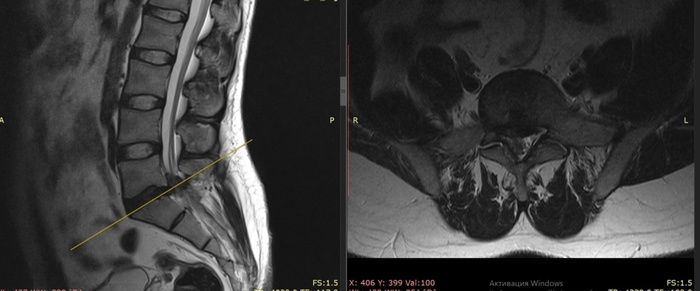

Так как с первой МРТ прошёл почти месяц, повторили МРТ.

А перидурита нет. Протрузия сидит себе.

Боли пошли.

В общем, пошел он лечиться у невролога.

Мораль: бежать оперироваться при любой грыже и протрузии не надо. И не всё, что болит - именно грыжа.